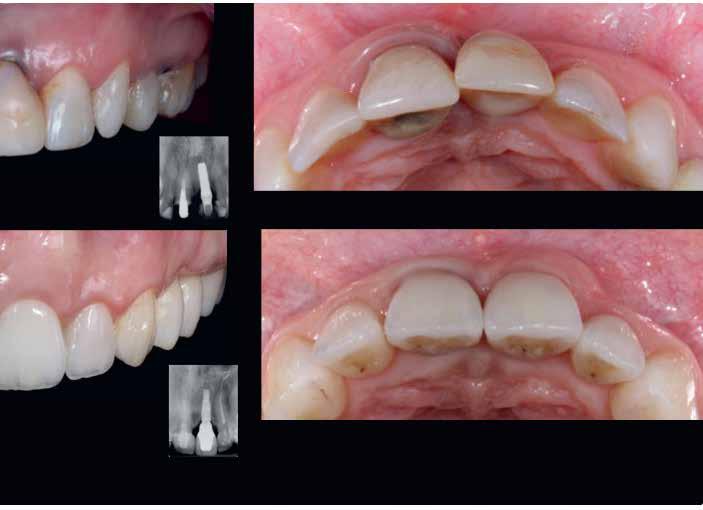

A szakirodalomban fellelhető eredmények alapján kerámia héjak ragasztására a kontaminációtól mentes, frissen vágott zománc felszín a legalkalmasabb. A hosszú távú sikeresség elérésének további feltétele a fogak konzervatív módon történő preparálása, továbbá a ragasztás kofferdám felhelyezésével biztosított, abszolút izolálásban történő kivitelezése. Úgy véljük, hogy a fenti faktorok biztosították a cikkben bemutatásra kerülő esetek – 5 évvel az átadás után megfigyelhető – sikerességét. A kofferdám izolálás alkalmazása számos előnyt biztosít a gyakorló fogorvos számára. Megakadályozza a munkaterület nyállal, vérrel, vagy szulkusz-váladékkal történő kontaminációját, és javítja a kezelendő területre való rálátásunkat. A fogak kerámia héjak ragasztása előtt történő izolálása azonban gyakran kihívást jelenthet a kevesebb klinikai tapasztalattal rendelkező fogorvosok számára. Jelen esetbemutatásban ismertetjük a kofferdám felhelyezésének lépéseit és néhány olyan gyakorlati tanácsot, amelyek jelentősen megkönnyíthetik a munkánkat, azokban az esetekben, amikor a második kisőrlőfogak közti területet kívánjuk kofferdám segítségével izolálni. A kofferdám kapcsok segítségével került rögzítésre, majd fogakat körülvevő széleit óvatosan az ínybarázdába forgattuk. A kerámia héjak számára előkészített fogakra ragasztás előtt egyenként kapcsokat helyeztünk annak érdekében, hogy a kerámia héjak rögzítése ideális körülmények között történhessen. A lépések részletes ismertetése segítséget jelenthet – a kevesebb klinikai tapasztalattal rendelkező fogorvosok számára – az abszolút izolálás megvalósításához szükséges lágyrészmenedzsment megértéséhez. Ezek az ismeretek rendkívül hasznosak lehetnek, ha a jövőben a kerámia héjak ragasztását megfelelő módon megvalósított kofferdám izolálás mellett kívánják kivitelezni. A cikkben ismertetett módszerek alkalmazásával az abszolút izolálás megvalósítható, a gumilepedő – vérzés nélkül – ínybarázdába történő beforgatására, és a ragasztáshoz szükséges idő csökkentésére.

A rendelésünkön egy 34 éves latin-amerikai nőbeteg azzal a panasszal jelentkezett, hogy a fogait „túl rövidnek” találja, és ezen felül a mosolyával sem volt megelégedve. Az anamnézisfelvétel alapján egészséges volt, elmondása szerint rendszeresen járt orvoshoz. Öt évvel korábban néhány hátsó fogát restaurálták. Páciensünk szájhigiénéje megfelelő volt,

a fogait rendszeresen ápolta. House klasszifikációja szerint, amely a pácienseket a fogászati kezelésekhez való attitűdjük szerint négy csoportba sorolja, a páciensünk a szabálykövető csoportba tartozott.

Az előzetes állapotfelmérést és a kezelés megtervezését követően a fogakat minimál invazív módon preparáltuk (1. a-b ábrák), majd az előkészített fogak ínybarázdáiba fonalbehelyező eszköz segítségével (113 Serrated Gingival Cord Packer, Hu-Friedy, Chicago, Illinois) teflonszalagot helyeztünk (Loctite Thread Seal Tape, Henkel Loctite Corp., Egyesült Államok), (1. c ábra). A hagyományos retrakciós fonalak helyett, a rugalmasságuk miatt előnyösebbnek tartjuk a teflonszalagok használatát. A kofferdámot (Dental Dam, Nic Tone, Bukarest, Románia) az előkészített fogakon kívül, az azoktól disztálisan elhelyezkedő egy-egy fognak megfelelően is perforáltuk.

Az oxigén inhibíciós réteg kialakulásának elkerülése érdekében a kerámiafelszíneket glicerin géllel (Liquid Strip, Ivoclar Vivadent, Schaan, Liechtenstein) borítottuk, majd ezeket a felszíneket ismét 20-20 másodpercen keresztül világítottuk. A végeredmény megfelelt a páciens esztétikai igényeinek (6. a. ábra). Az átadott restaurátumok épségének megőrzése érdekében, a páciens számára éjszakai fogvédő sín készült. Az ötéves kontroll alkalmával megállapítottuk, hogy az elvégzett kezelésünk továbbra is sikeresnek tekinthető (6. b. ábra)

Az általunk alkalmazott adhezív rendszerek hatékonyságát nagymértékben növelhetjük azáltal, hogy a fogakat minimál invazív módon, azaz csak zománcon belül preparáljuk, és a kerámia héjakat kofferdám izolálásban ragasztjuk. Jelen esetismertetésünknek az volt a célja, hogy bemutassuk, hogyan lehet az adekvát módon kivitelezett kofferdám izolálással megelőzni

a munkaterület nyállal, vérrel vagy szulkusz-váladékkal történő kontaminációját. A megfelelő méretben kialakított perforációs nyílások és köztük lévő optimális távolság elengedhetetlen ahhoz, hogy a kofferdámot ideális módon tudjuk felhelyezni. Ezzel az esettel azt is bizonyítjuk, hogy a gumilepedő levegőfújással, fogselyemmel és teflonszalagok segítségével történő beforgatásával az ínyvérzés kialakulását el lehet kerülni. Ismételten szeretnénk hangsúlyozni, hogy a megfelelő kofferdám kapcsok használata nélkül nem tudtuk volna a preparált csonkszélt a gumilepedő szélétől eltartani. A kezelés során elért eredményeket jól alátámasztotta, hogy a páciens az ötéves kontroll vizsgálat során teljesen elégedett volt.